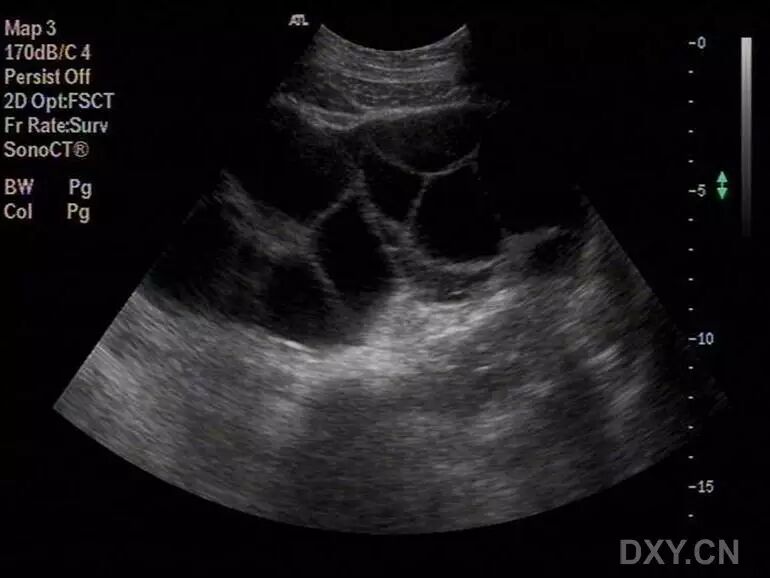

病例2(由丁香园注册用户「荷瓣111」提供):患者女,28岁,结婚5年未孕,应用促排卵药治疗2个月后,自觉腹部膨隆,呼吸困难。

超声所见如下图所示:

图1~3 显示子宫正常,盆腹腔可见两个相依的囊性肿物,其内见多条光带分隔,子宫被压在增大的卵巢下方

图4 显示肝肾区的腹腔积液